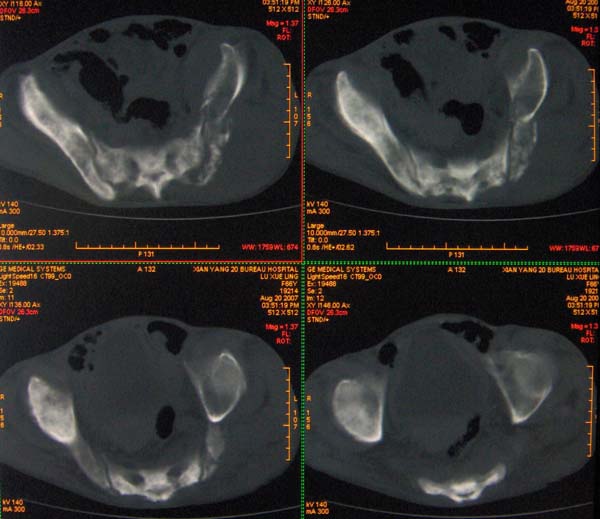

以下是引用ybing在2007-8-22 20:31:00的发言:[br]左侧髂骨溶骨样破坏;软组织肿块形成;其内未见肿瘤骨考虑纤维肉瘤或滑膜肉瘤不除外转移瘤

以下是引用qiushi在2007-8-22 21:39:00的发言:[br]双侧髂骨、骶骨侧快呈溶骨样骨质破坏,边缘模糊,左侧髂骨见骨折线,左侧髂部见软组织块影。考虑骨纤维肉瘤(中央型)伴病理性骨折,不排除骨髓瘤。建议本--周氏蛋白检查。[br] 鉴别点:[br] 骨纤维肉瘤,中央型者示边缘模糊的囊状溶骨破坏,一般无骨膜反映,可膨胀变形,突破骨皮质可形成软组织肿块,或并发病理性骨折。[br] 骨髓瘤,常表现为广泛的骨质疏松,皮质变薄或破坏,呈粟栗状、穿凿状、鼠咬状骨质破坏,边缘清晰,周围无硬化。[br] 骨转移瘤(溶骨型),表现为虫噬样、泡沫状圆形或卵圆形破坏区,很少出现软组织块影。[br][br][本贴已被 qiushi 于 2007-8-23 6:20:19 修改过]